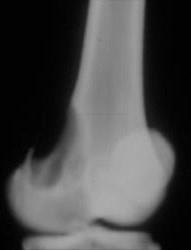

问题 男,22岁,左侧膝部肿胀,疼痛2个月余,请结合影像学检查,选出最可能的诊断 ( )

选项 A、动脉瘤样骨囊肿 B、软骨肉瘤 C、骨肉瘤 D、骨髓炎 E、骨脓肿

答案 A